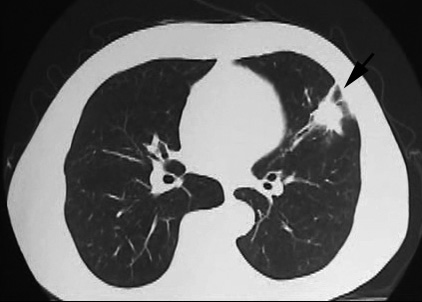

今月定期受診で1年ぶりにchest X-pを撮影. 両肺野に多発結節影が指摘されて受診となった.

chestX-pとCT.サムネイル画像クリックで大きな画像がみられます.